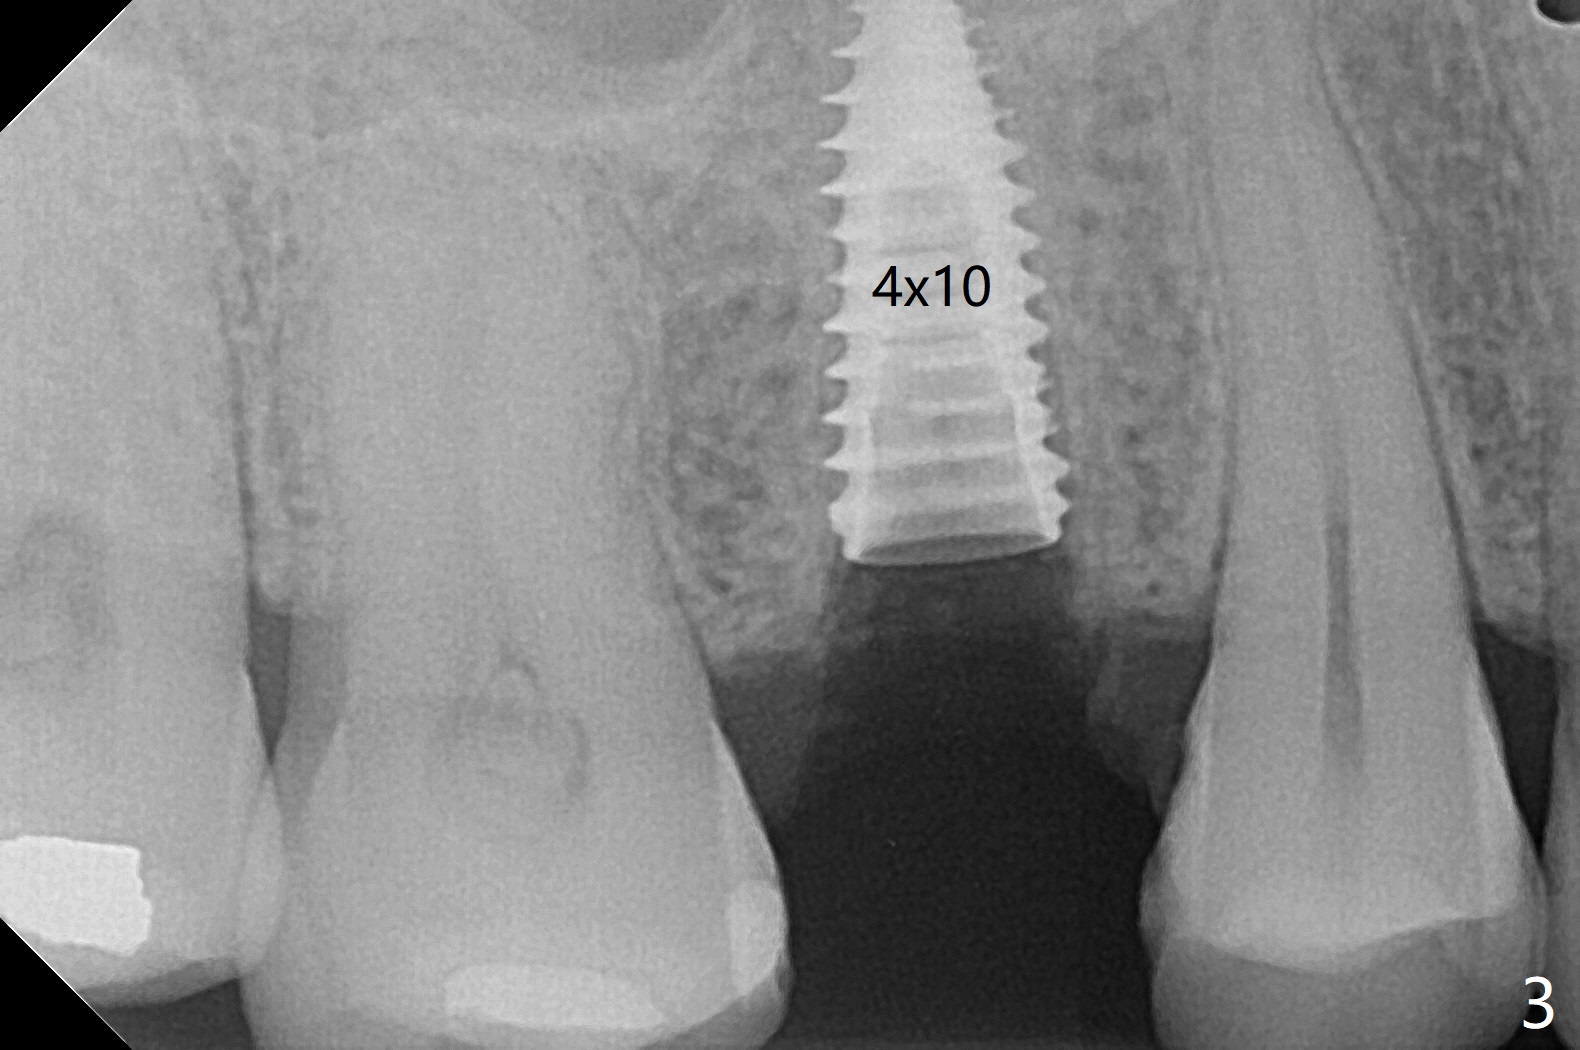

40岁女右上5近中龈下龋齿(图一),要求拔除植牙,上颌窦底板已经破坏穿孔,但是窦膜完整(图二)。清创后,放置PRF膜和粘性骨粉,用挖匙和上颌窦充填器尽量往上面推。然后放置导板,使用2.2x7.3 和3.0x7.3毫米钻头完成钻洞,可能无意中把骨粉推入上颌窦,之后利用报废植体(图三,四)完成提升,同时修补根尖缺损(利用之前放置的骨粉,图四:*,与图五(术前)对比)。当报废植体取出时,植牙窝已经形成,再放入少量骨粉,植入同样大小(之前扭力高)正式植体(不同品牌,图六,七),这时扭力低,放置愈合帽和骨粉(图七,八),以及6-9个月吸收膜,使用牙周胶水固定(图九),最后牙周敷料。术中术后几个小时没有上颌窦膜破裂迹象。术后一周牙周敷料松动,造成不适,去除时,膜好像粘附于敷料一起去除,骨粉暴露(图十),使用树脂敷料固定。后者术后一个月去除,因为局部有臭味。术后4个月切开放置愈合基台(图十一),术后五个月放置修复基台(图十二),使用塑料袖取模。术后5.5月同时放置牙冠和基台,十分顺手,口内粘固,之后同时取出,除去多余粘固剂,然后拧紧30Ncm(厂家推荐35 Ncm),一切非常顺利,觉得拍摄X光片是多余的。美中不足的是开孔(access hole)偏腭侧(图十二;由于自由手植入植体,与设计对比)。